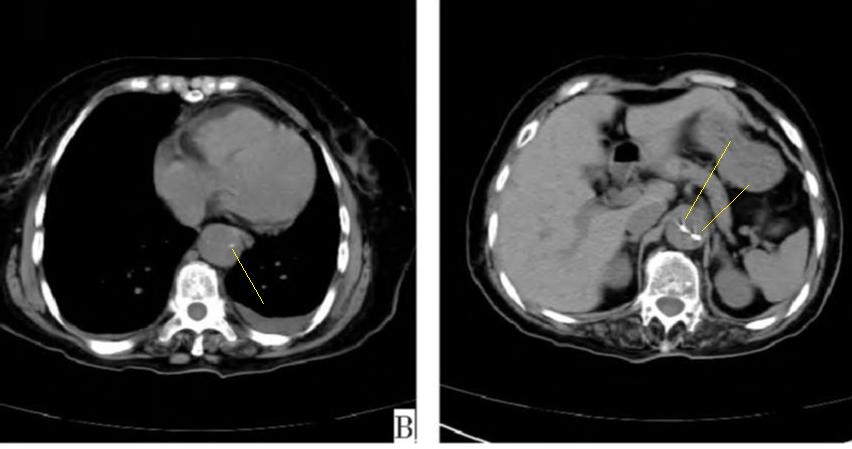

下图的胸部CT平扫,有什么致命的问题?

图7

仔细一看,主动脉里面有线样阴影!并且,线样阴影两边的密度一高一低!

图8

增强CT一看,主动脉夹层,密度相对高的是流动的血液!

图9